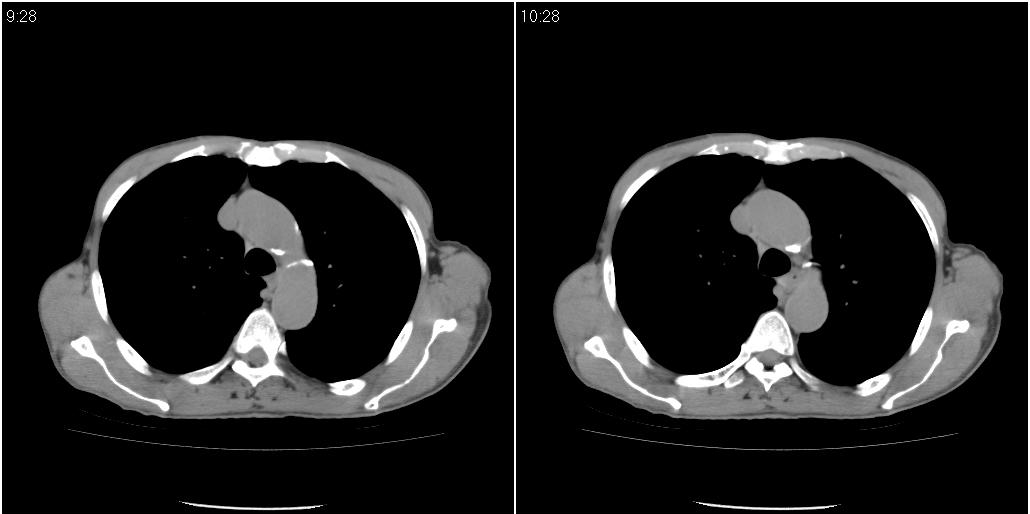

标题: CT25416:男性,70岁。胸片发现右下肺斑片状阴影 [打印本页]

标题: CT25416:男性,70岁。胸片发现右下肺斑片状阴影

以下是ct检查的情况:

考虑右肺下叶炎症可能性大?未除占位,建议增强。右下肺肺不张

右下胸壁皮下气肿。